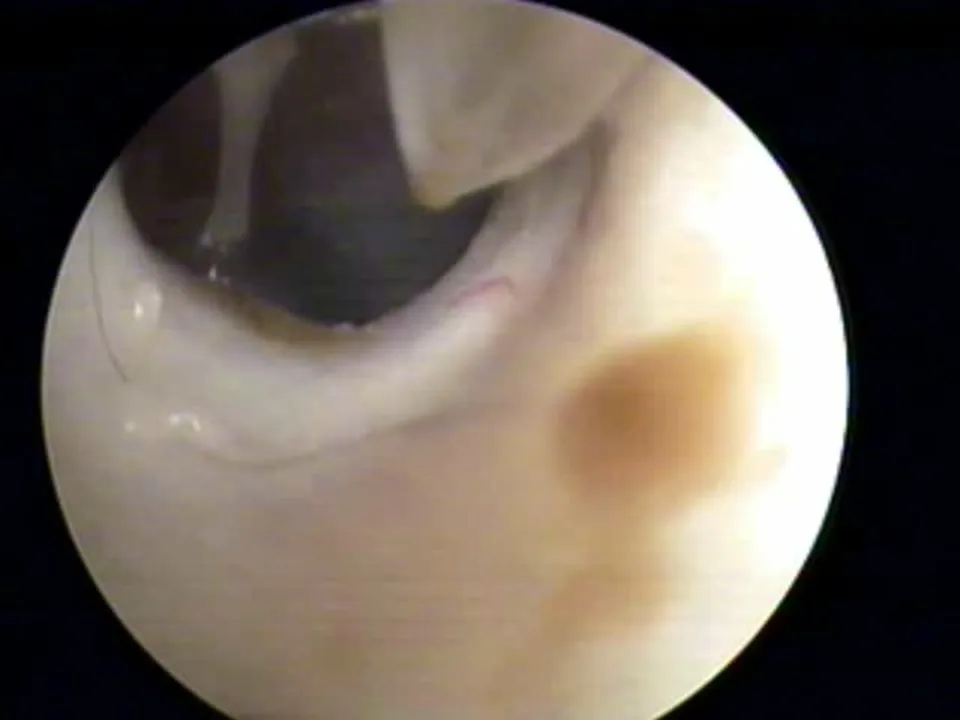

Visualization of fluids (eg, blood, pus, mucus, serum) behind the eardrum in the middle ear (Figure 2)

FIGURE 2 Left middle ear inflamed with exudate and blood behind eardrum (left). The normal right eardrum is shown for comparison (right).